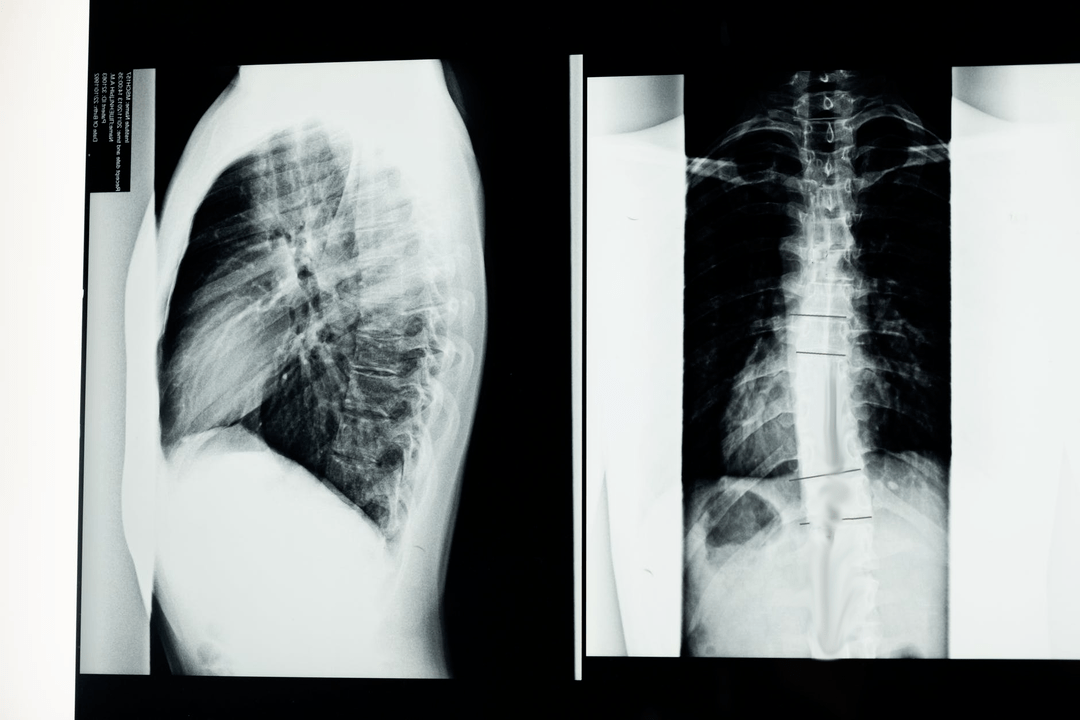

Înainte de a începe studiile de diagnostic, neurologul colectează istoricul medical al pacientului și studiază cu atenție plângerile acestuia. Osteocondroza are simptome comune cu alte boli, de aceea este important să putem diferenția patologiile. Studiile cu raze X vor ajuta la confirmarea diagnosticului de osteocondroză: radiografie, mielografie și tomografie computerizată.

Un sondaj cu raze X vă permite să obțineți o imagine cu raze X a coloanei vertebrale sau a unei secțiuni a acesteia. În acest fel, medicul poate determina locația afectată de boală. Pentru claritate, vom explica modul în care osteocondroza poate fi determinată prin radiografie: imaginea va arăta o îngustare a discului intervertebral, prezența creșterilor osoase (osteofite) sau o modificare a formei segmentului spinal.